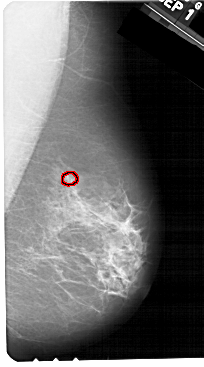

A_1328_1.RIGHT_CC

RIGHT_CC LINES 5491 PIXELS_PER_LINE 3016 BITS_PER_PIXEL 12 RESOLUTION 43.5 OVERLAY

FILE: A_1328_1.RIGHT_CC.OVERLAY

TOTAL_ABNORMALITIES 1

ABNORMALITY 1

LESION_TYPE CALCIFICATION TYPE PLEOMORPHIC DISTRIBUTION CLUSTERED

ASSESSMENT 4

SUBTLETY 5

PATHOLOGY BENIGN

TOTAL_OUTLINES 1

BOUNDARY